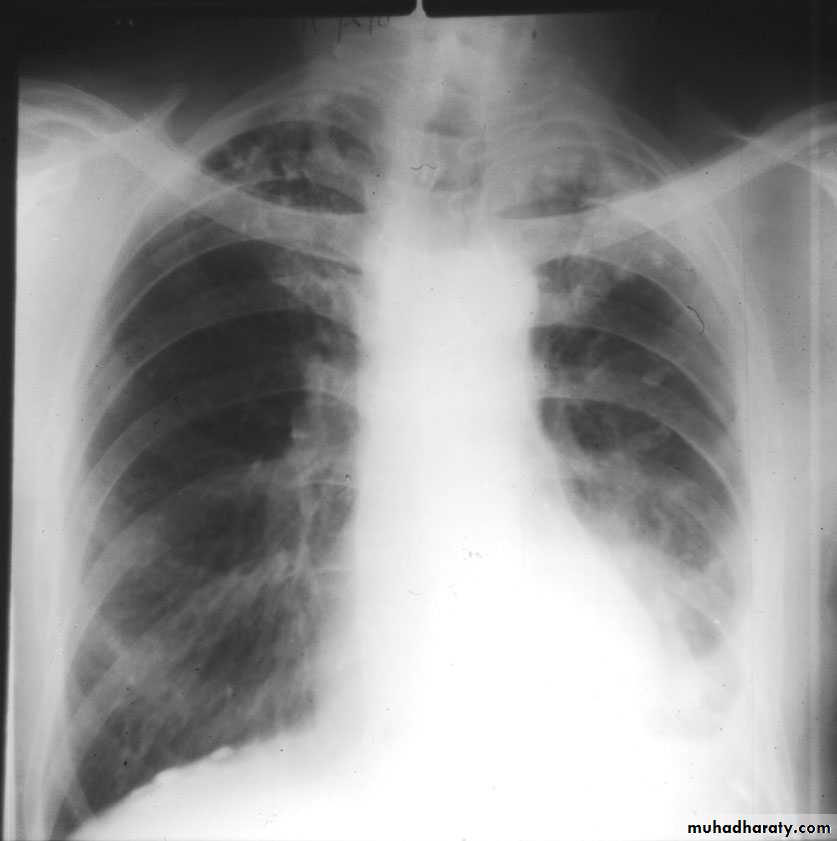

X-ray views1- PA view.

NORMAL PA view